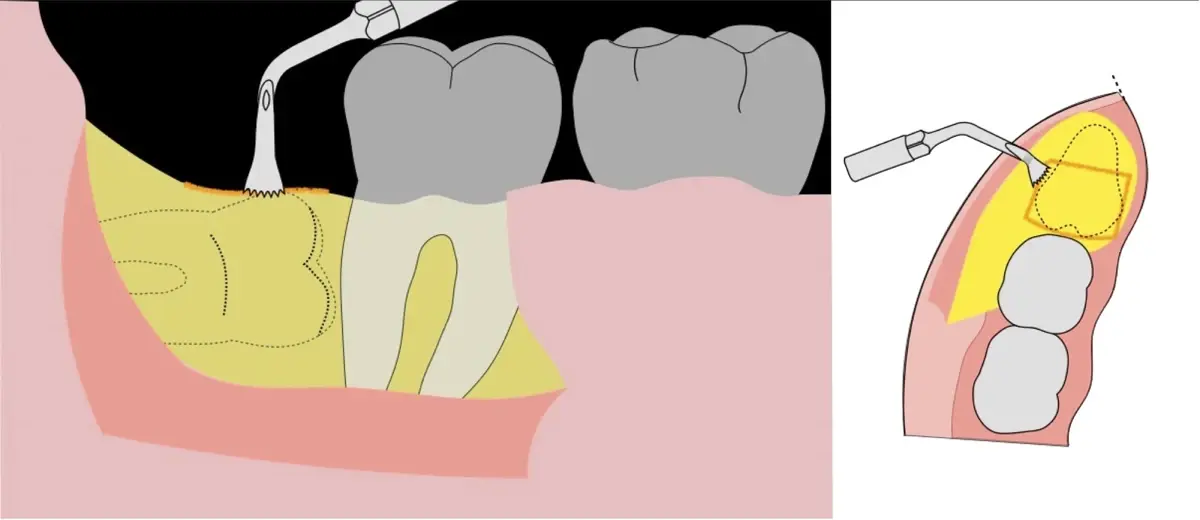

Figura 8. Odontosección mediante fresa de alta rotación y/o inserto de corte de piezoeléctrico. Posteriormente se procede al ensanchamiento del espacio pericoronario con el periótomo de piezoeléctrico para facilitar la avulsión de la pieza dentaria.

Figura 9. Avulsión de la parte coronaria de la tercera molar.